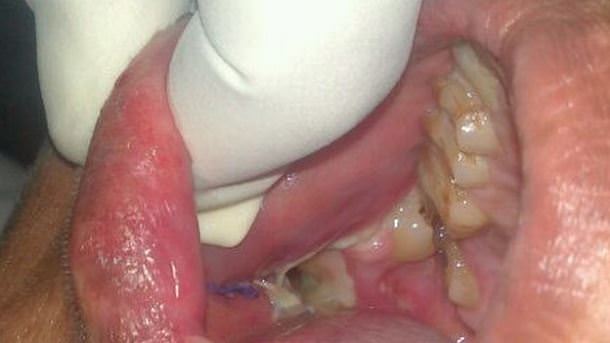

Un chico que sufre una extraña anomalía acudió al médico tras sufrir de dolores en su mandíbula por al menos un año y medio. Ashik Gaval, de 17 años tuvo que ser intervenido quirúrgicamente para extraerle 232 dientes debido a que sufría un odontoma compuesto, originado por un tipo de tumor en la estructura dental o en las estructuras embrionarias que desarrollan los dientes.

El resultado de su extraño caso clínico es que Ashik desarrollaba dientes de una forma anómala, ya que incluso después de haberle sido extraído 232 dientes de distintos tamaños los doctores le dejaron 28 en su boca. Sin embargo la operación que duró cerca de siete horas no es definitiva y los doctores le advirtieron que es posible que su tumor benigno genere nuevos dientes.   extraen_232_dientes_09 extraen_232_dientes_08 extraen_232_dientes_07 extraen_232_dientes_06 extraen_232_dientes_05 extraen_232_dientes_04 extraen_232_dientes_03 extraen_232_dientes_02 extraen_232_dientes_01